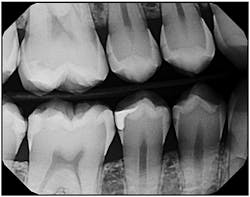

1. Improved image quality — When I used traditional film, once the X-ray was taken and developed, that was it. If the solution needed to be changed or the temperature varied, we had to live with the consequences of an image that was either too light or too dark. But due to the nature of digital imaging, I now expect consistent quality. To focus on a certain area, I can zoom in or change contrast. So much research and development goes into generating quality images. For instance, DEXIS, the brand I chose, notes that its images are made in 16,000 shades of gray.* That is a large number of shades for bringing out the subtle variations in density. When I need even more sharpness, I use the ClearVu image enhancement tool, which is so much easier than holding a small film X-ray up to the light. Even a patient who is not trained in reading X-rays can look at an image on the monitor and see small details, such as fractures.